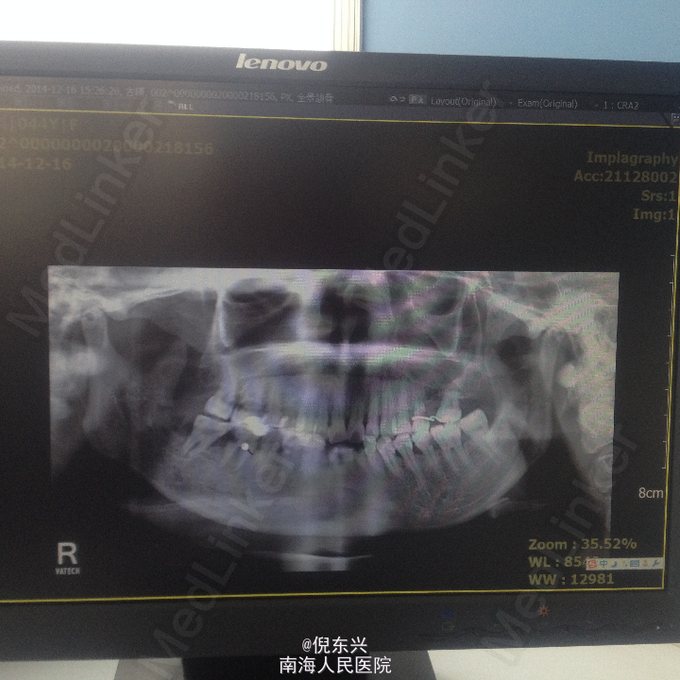

主诉:右侧颌下区有瘘口数周伴流脓 现病史:患者因鼻咽癌行局部放疗,放疗期间右侧后牙疼痛未治疗,数周前出现右侧颌下区皮肤肿胀,自行破溃,一直流脓,口服消炎药,效不佳

查体见:患者右颌下区见一瘘口,有脓血样液体流出, 全景结果是:右侧下颌升支及下颌角区可见骨质有吸收,47可见远中有龋坏。

诊断:放射性骨髓炎 处理:长期换药,待死骨分离